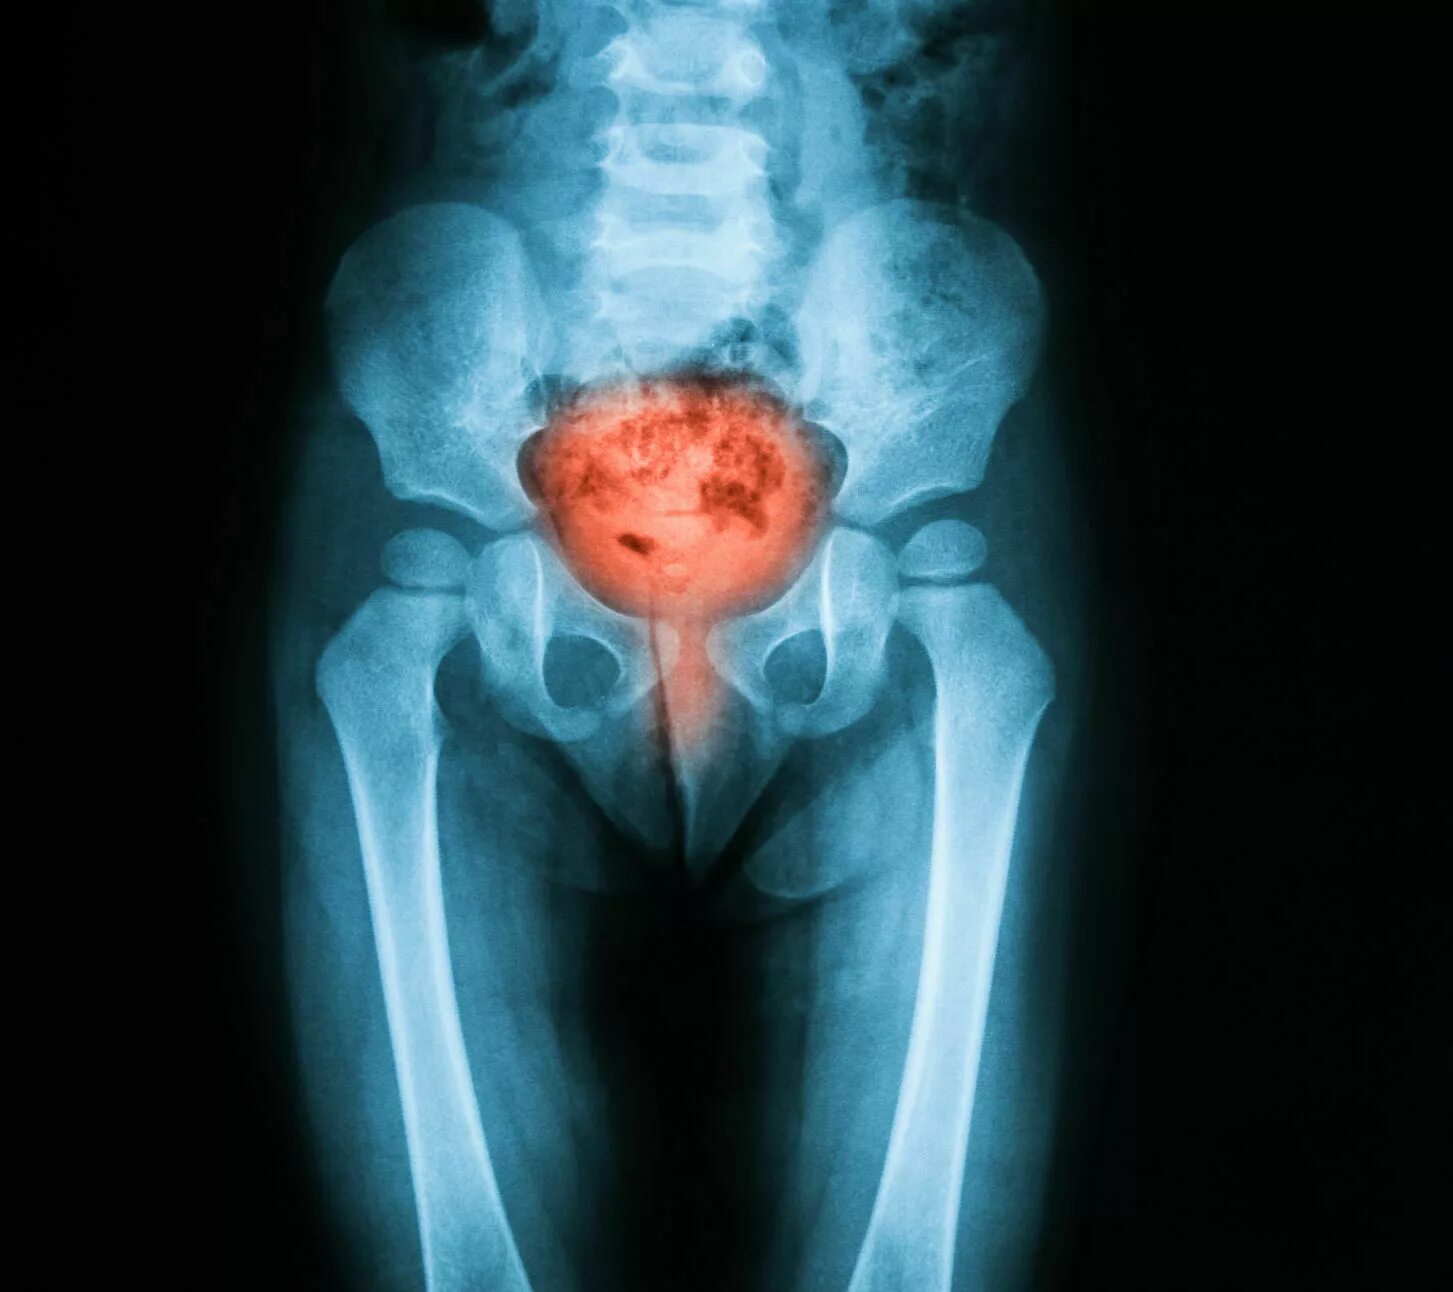

Резь в мочеиспускательном канале